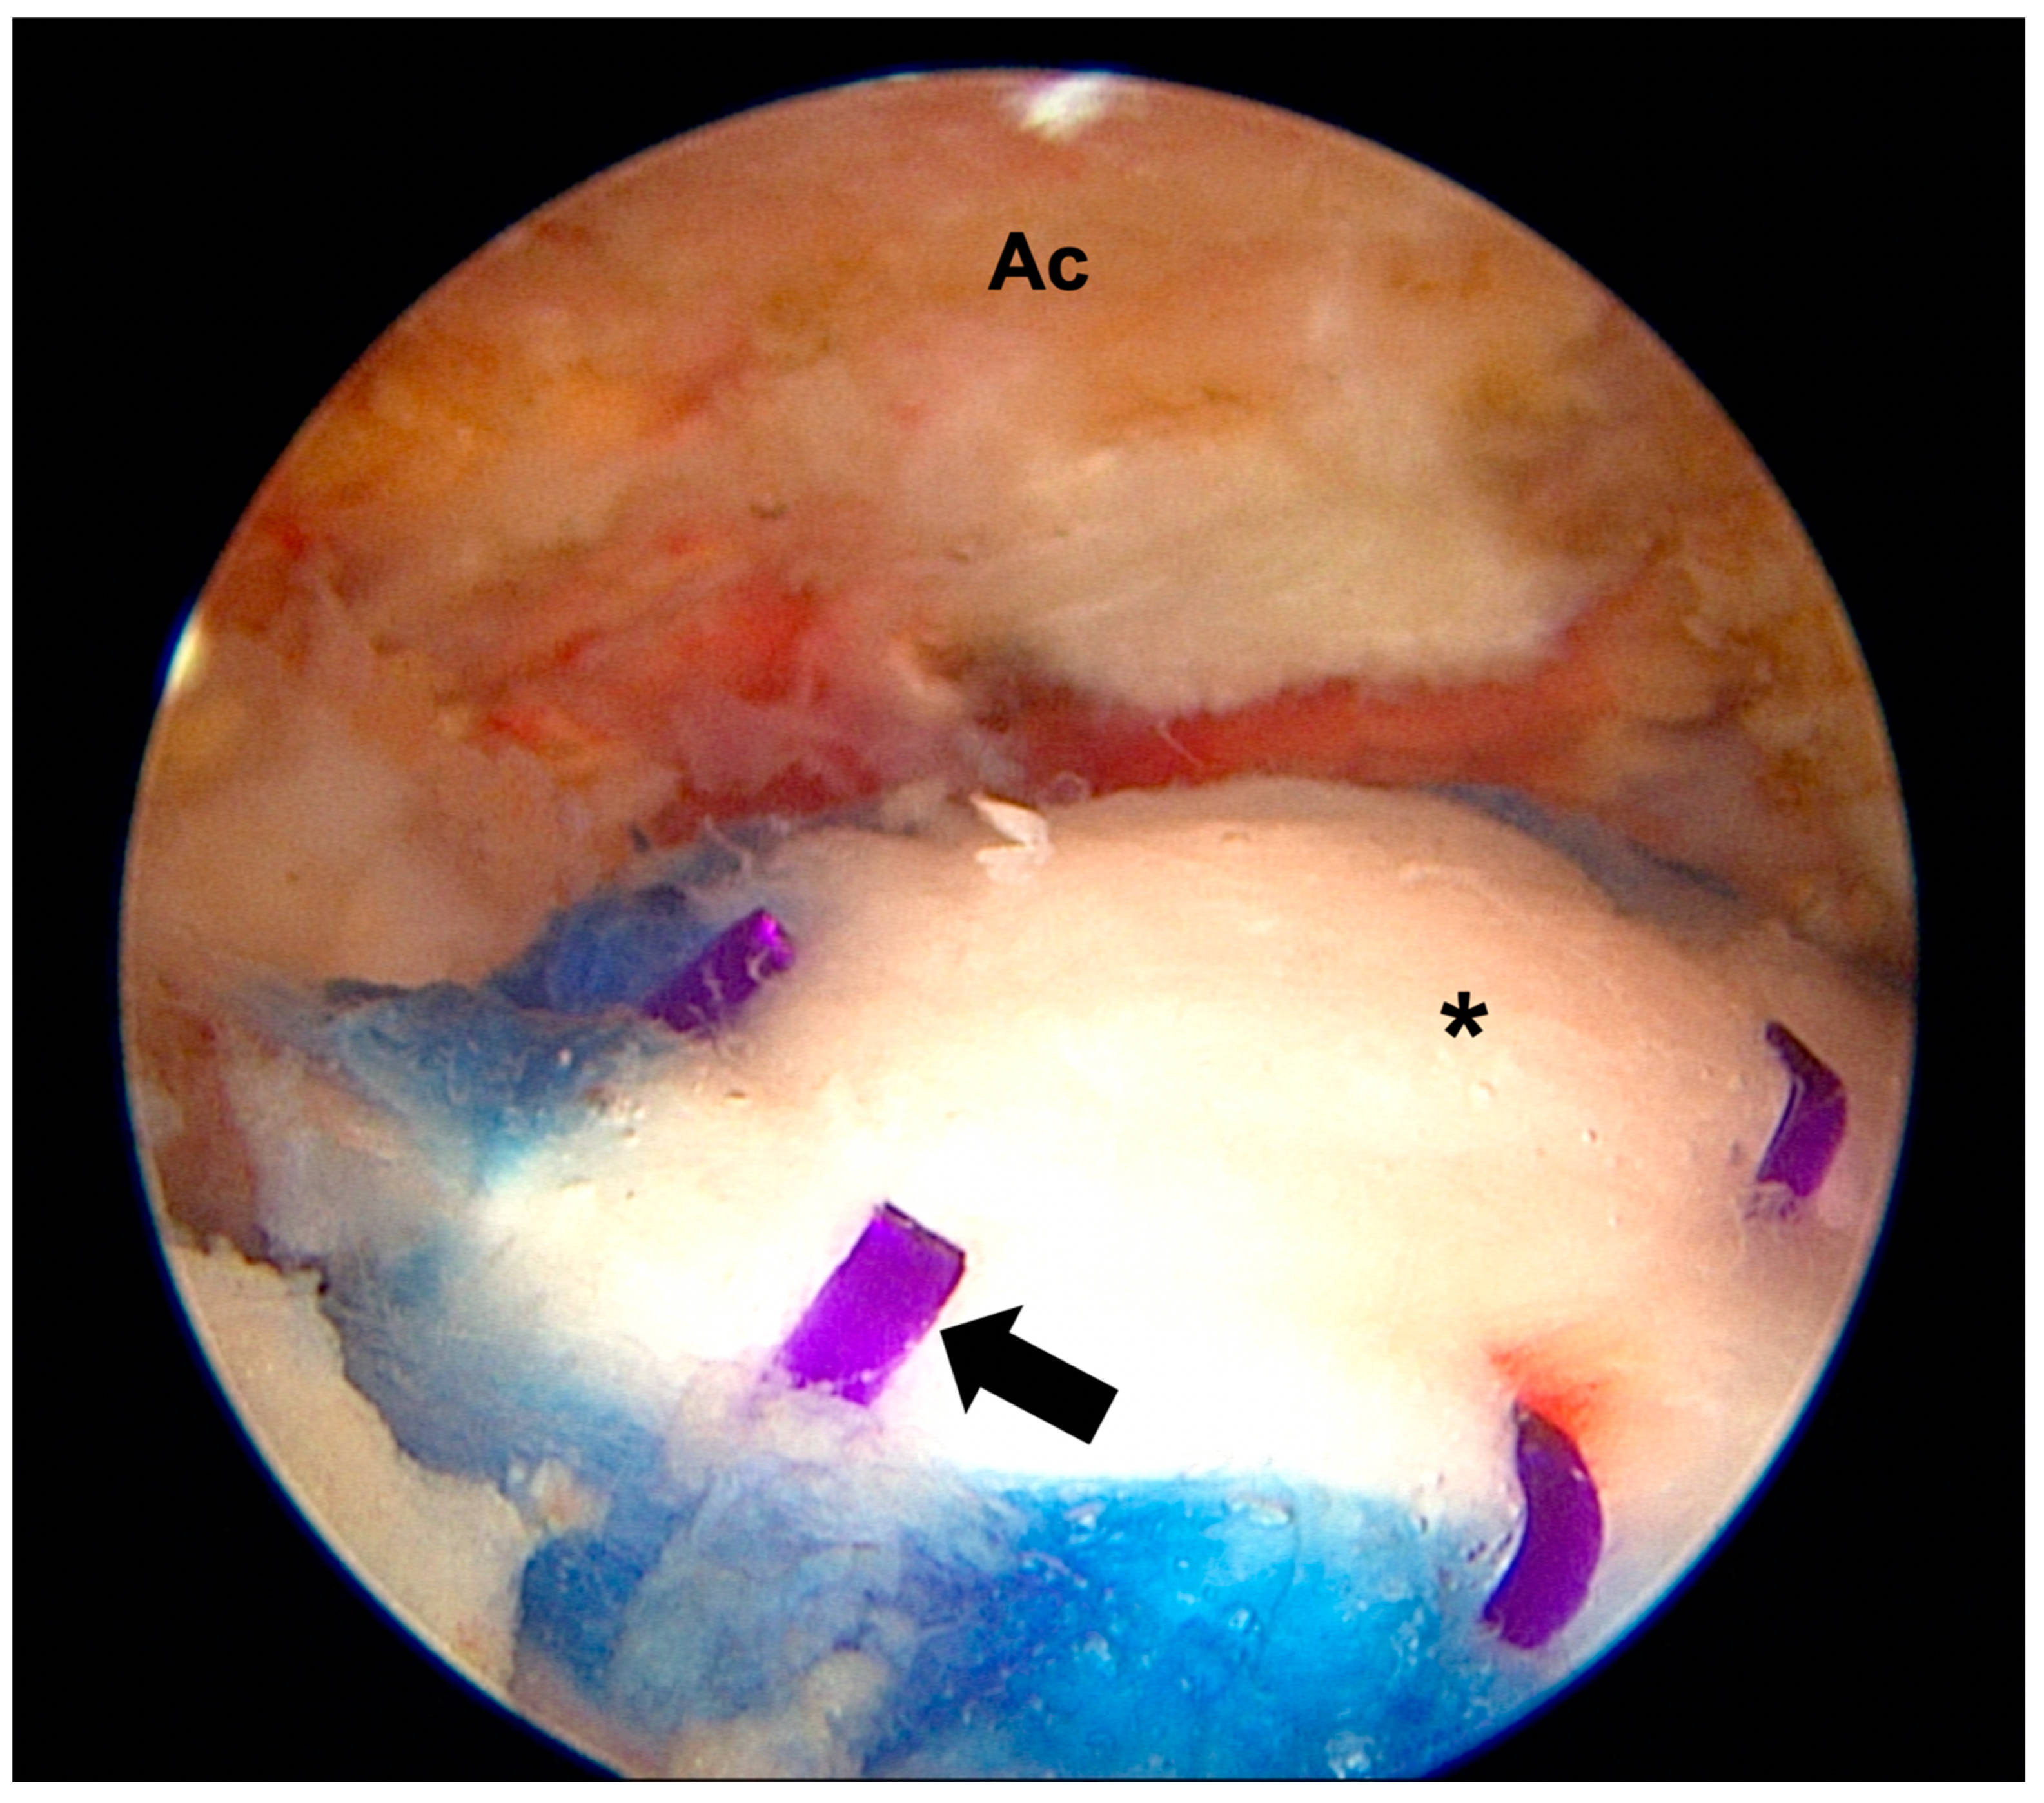

- Ruiz Ibán, M.Á.; García, N.M.; Moros, M.S.; Diaz, H.J.; Hernando, S.A.; Ruiz, D.R.; Vaquero, C.C.; Rosas, O.M.L.; Del Monte, B.G.; Ávila, L.J.L. Augmentation of a Transosseous-Equivalent Repair in Posterosuperior Nonacute Rotator Cuff Tears with a Bioinductive Collagen Implant Decreases the Retear Rate at One Year: A Randomized Controlled Trial. Arthrosc. J. Arthrosc. Relat. Surg. 2023, 40, 1760–1773. [Google Scholar] [CrossRef] [PubMed]

- Camacho-Chacon, J.A.; Cuenca-Espierrez, J.; Roda-Rojo, V.; Martin-Martinez, A.; Calderon-Meza, J.M.; Alvarez-Alegret, R.; Martin-Hernandez, C. Bioinductive collagen implants facilitate tendon regeneration in rotator cuff tears. J. Exp. Orthop. 2022, 9, 53. [Google Scholar] [CrossRef]

- Bokor, D.J.; Sonnabend, D.; Deady, L.; Cass, B.; Young, A.; Van Kampen, C.; Arnoczky, S. Evidence of healing of partial-thickness rotator cuff tears following arthroscopic augmentation with a collagen implant: A 2-year MRI follow-up. Muscles Ligaments Tendons J. 2016, 6, 16–25. [Google Scholar] [CrossRef]